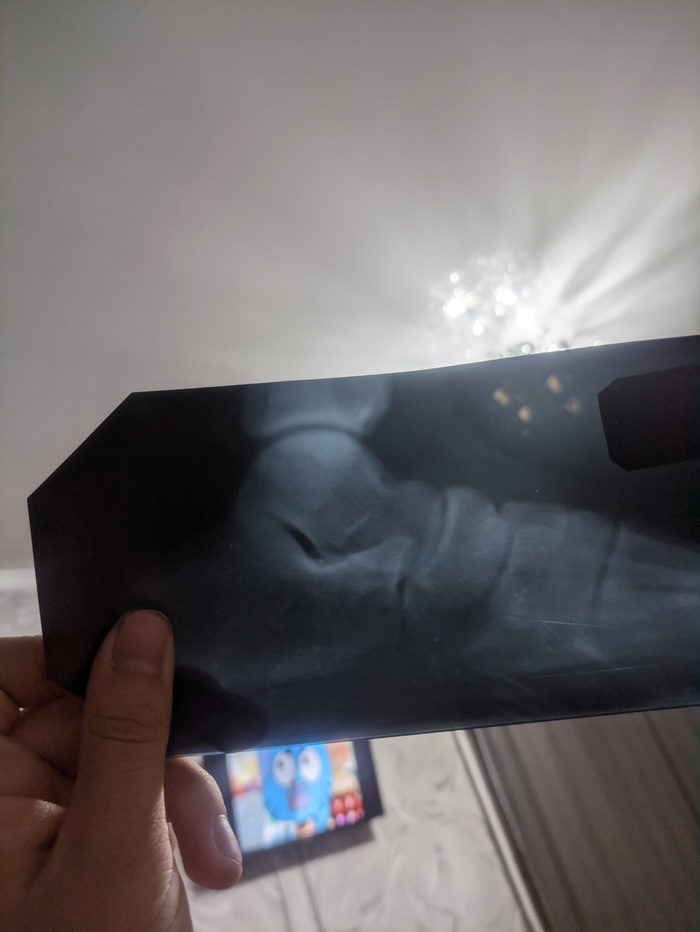

Как понять открыты ли зоны роста по снимку ?

Есть ли тут те кто разбираются в этом?

Появился интерес прибавить в росте.Ну и вот снимки 6 месячной давности попались под руку и вроде как я понял,знающие люди могут определить открыты ли зоны роста по всяким таким снимкам.Знаю что вроде по ладоням смотрят,но лень идти делать целенаправленно из за этого снимки